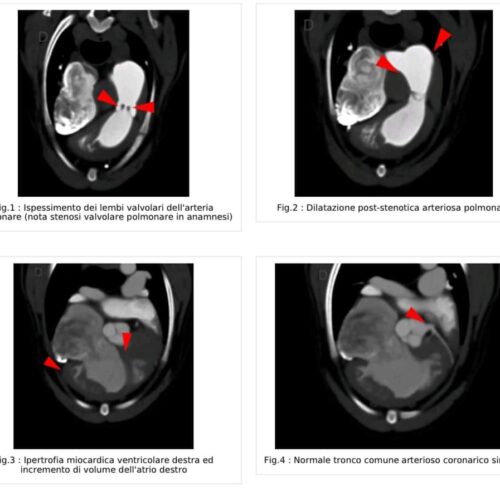

CARDIOTC in un maltipoo di 2 anni con stenosi polmonare

🔈 CARDIOTC in un maltipoo di 2 anni con stenosi polmonare!! Studio TC specialistico per lo studio del cuore. **** TAC E RISONANZA MAGNETICA DI REFERENZA PER COLLEGHI IN CAMPANIA**** Info e prenotazioni: www.clinicaveterinariadiaz.it